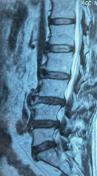

核磁显示腰4/5、腰5骶1椎管狭窄

61岁男性患者,腰4/5及腰5骶1两个节段椎管狭窄,腰痛伴左下肢放射性疼痛10年,伴有间歇性跛行,影响日常生活,保守治疗无效,但身体并发多种内科疾病,无法行开放手术,局麻下行微创椎间孔镜双节段减压。